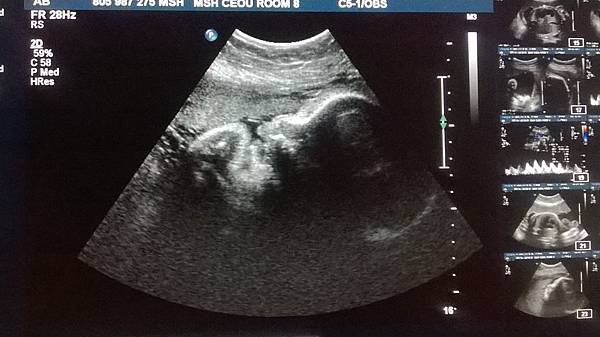

【峰迴路轉超音波】

這不是比比第一次照超音波,但卻是我們拿到的第一張超音波照。

在台灣,懷孕的朋友都會迫不及待與大家分享自己寶寶的超音波照。這些照片不知道是醫院主動提供,還是媽媽們向醫院買的(不好意思,沒在台灣做過產檢,有人可以回答我嗎?)。我在多倫多照超音波的經驗是,醫生不會自己照,她會給我一張影像中心的單子,我再跟醫院配合的影像中心預約時間前往照超音波。檢查完畢之後,影像中心會將各種指標記錄成2~3頁報告,傳回給我的醫生。不確定影像是否也會一併給醫生,不過我從兩個醫生的病歷夾裡,都沒瞄到任何類似影像資料。醫生也沒主動給我看過,只說 Good. Any question?

第一次去照超音波時(第七週),原本滿心期待可以拿到生平第一張的寶寶照。結果ultrasound techinician自顧把該量的指數都量完後,再把螢幕轉向我,跟我解釋哪裡是頭、哪裡是腳、一閃一閃的小點是心跳,就結束了。機器旁邊沒有印表機直接跑一張寶寶照來相贈,technician也沒有提到任何關於要不要印影像留念的問題。我說了謝謝,離開診間。心裡還抱著一絲希望,認為也許櫃台那邊會印,等我離開時一併給我。

懷孕20週時,我在Mt. Sinai照了第一次超音波,但是是整個孕期的第三次。前兩次莫名的walk-in clinic幫我安排照超音波,我懷疑第一次的結果被弄丟了。第二次本來要判讀唐氏症,但超過週數,就照心酸的。這一次有一個任務,就是要看寶寶的性別!

之前想跟寶寶說話,但不知道它是男是女,沒辦法取小名,也不知道該稱呼它he還是she,所以我個人非常期待這次的結果揭曉。

Mt. Sinai的超音波部門跟婦產科在同一個地方,也是須要另外預約,但不用再打電話,就拿著醫生給的單子,走到超音波櫃檯預約就可以了。預約完再回到醫生助理那邊告訴她約到的時間,依據照超音波的時間往後推至少一週,預約下次產檢。

那天是預約下午兩點照超音波,匆匆吃完午餐,一點半不到就跟黃先生匆匆出門(你問:黃先生為何在家?因為他的工作錢少、事多、離家進,可以天天回家吃午餐)。到了醫院正好一點五十分,到櫃檯報到完,等待叫號 ─ 依然是「查理王」(典故請見前幾篇懷孕文)。